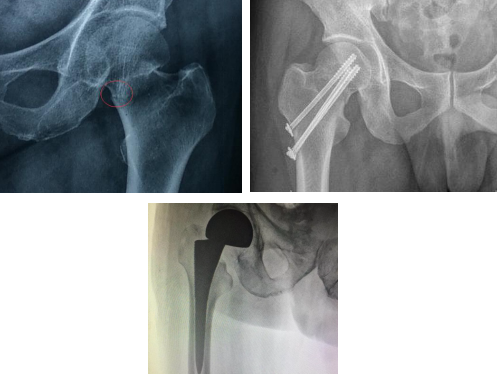

股骨颈骨折是指股骨头下至股骨颈基底部之间的骨折,是临床的常见病、多发病,可见于各个年龄段,以中老年患者发病率最高。在临床中,根据骨折线位置的不同,多分为:头下型、经颈型和基底型。

股骨颈骨折的手术方式很多,如空心螺钉固定、钢板螺钉固定以及人工髋关节置换。对于老年人,由于骨质疏松,钢板及螺钉把持力不足,钢板或螺钉固定效果较差,存在骨折不愈合和股骨头坏死的风险。因此,对于65岁以上的老年人完全型股骨颈骨折,我们建议进行人工髋关节置换手术,并根据患者年龄、髋臼发育情况、骨质疏松程度等选择全髋关节置换或人工股骨头置换术。

人工髋关节置换术是目前较成功的手术之一,是利用人工材料,替换已病损的髋关节,充分模拟正常的髋关节结构特点,恢复其运动功能。其治疗效果经过三十多年的临床实践,已经得到充分的肯定,可有效的缓解关节疼痛、矫正畸形、恢复和改善关节的运动功能,快速消除上述疾病给患者带来的痛苦,明显提高患者的生活质量。患者术后第1天就可以下地活动,有效的避免了长期卧床给老年人带来的并发症。